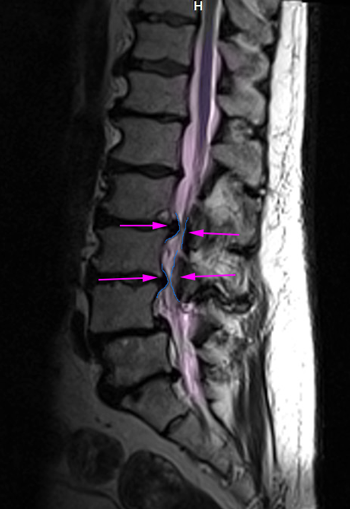

SpinalStenosis2

Η οσφυϊκή πεταλεκτομή είναι η αφαίρεση του οπισθίου μέρους (το οποίο αθροιστικά ονομάζεται πέταλο) ενός ή περισσοτέρων σπονδύλων της οσφυϊκής μοίρας της σπονδυλικής στήλης προκειμένου να αποσυμπιεστούν τα οσφυϊκά νεύρα. Η επέμβαση γίνεται σε ασθενείς με στένωση του σπονδυλικού σωλήνα εκφυλιστικής, τραυματικής ή ογκολογικής αιτιολογίας. Η αφαίρεση του πετάλου γίνεται με οπίσθια προσπέλαση, με τομή δέρματος στο μέσο της ράχης, στο ύψος της στένωσης. Οι επιπλοκές είναι λίγες και όχι συχνές.

Η οσφυϊκή πεταλεκτομή είναι όχι μόνο μια αποσυμπιεστική επέμβαση αλλά και ο κύριος τρόπος προσπέλασης του σπονδυλικού σωλήνα για χωροκατακτητικές εξεργασίες. Η συνηθέστερη ένδειξή της είναι η εκφυλιστική στένωση του οσφυϊκού σπονδυλικού σωλήνα και η πίεση που ασκείται από αυτήν στα οσφυϊκά νεύρα, η οποία εκφράζεται με νευρογενή διαλείπουσα χωλότητα ή/και ισχιαλγία στο ένα ή και τα δύο κάτω άκρα. Άλλες ενδείξεις είναι η στένωση του σπονδυλικού σωλήνα που προκαλείται από κάταγμα ή υπεξάρθρημα οσφυϊκού σπονδύλου, από σπονδυλολίσθηση, ή από όγκους. Τέλος, με οσφυϊκή πεταλεκτομή μπορούν να εξαιρεθούν και σπανιότερες σε συχνότητα χωροκατακτητικές εξεργασίες όπως τα αιματώματα του σπονδυλικού σωλήνα και οσφυϊκά επισκληρίδια εμπυήματα.

Η οσφυϊκή πεταλεκτομή πραγματοποιείται με τομή στη μέση γραμμή της ράχης στο ύψος της στένωσης. Το μήκος της εξαρτάται από τον αριθμό των πετάλων που πρέπει να αφαιρεθούν. Αυτά παρασκευάζονται και αφαιρούνται. Στις εκφυλιστικές στενώσεις πρέπει συνήθως να αφαιρεθεί και μέρος των μικρών αρθρώσεων της σπονδυλικής στήλης, γιατί είναι κατά κανόνα υπερτροφικές και συνεισφέρουν στην στένωση του σπονδυλικού σωλήνα και σε πολλές περιπτώσεις εκτελείται και δισκεκτομή όταν υπάρχει και σημαντική κήλη μεσοσπονδυλίου δίσκου ως συνεισφέρων παράγοντας στη στένωση. Η αποσυμπίεση του σπονδυλικού σωλήνα ακολουθείται πάντα και από αποσυμπίεση των νεύρων στα τρήματα εξόδου τους από την σπονδυλική στήλη, μια συνοδό επέμβαση που ονομάζεται τρηματεκτομή.